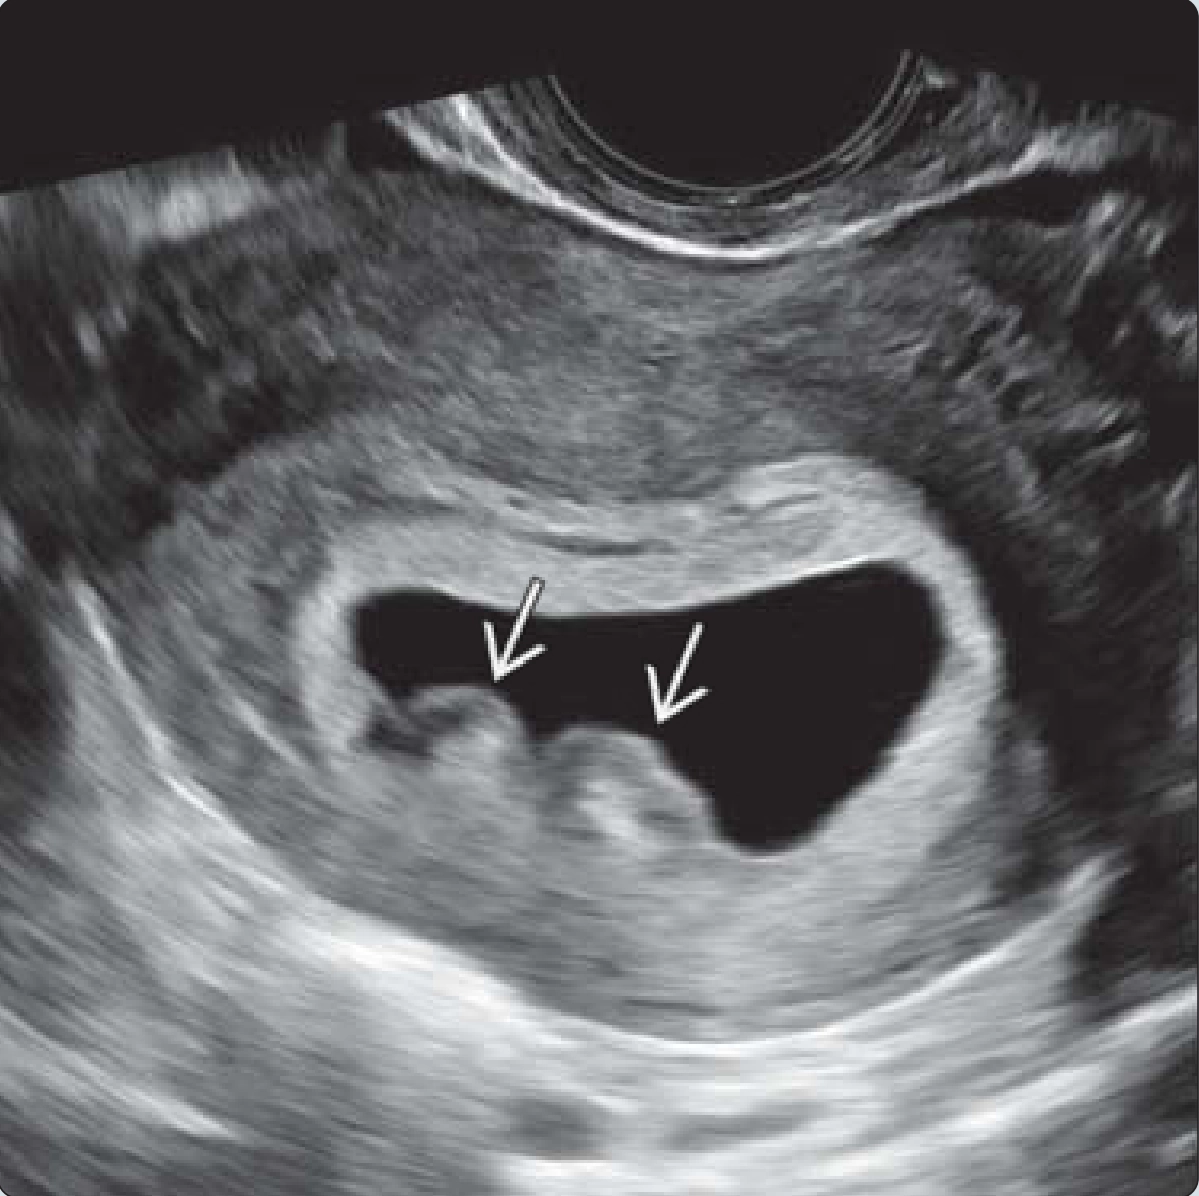

Tụ máu dưới màng nuôi (Tụ máu quanh túi thai)

Khối phồng màng đệm (Chorionic Bump)